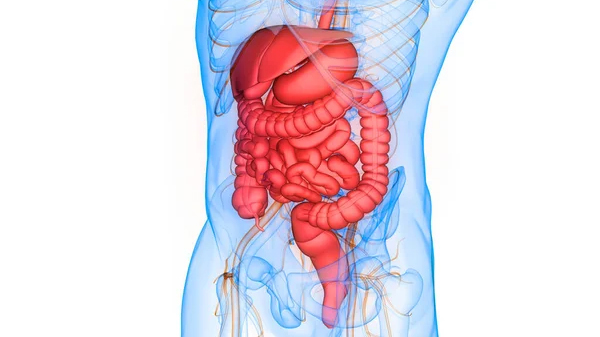

El síndrome de intestino irritable (SII) es un trastorno gastrointestinal crónico que afecta el funcionamiento normal del intestino. Las personas con SII pueden experimentar síntomas como dolor abdominal, hinchazón, estreñimiento y diarrea. Aunque se desconoce la causa exacta del SII, se cree que puede estar relacionado con factores como el estrés, la dieta y la sensibilidad del intestino.

No existe una cura para el SII, pero los síntomas se pueden controlar mediante cambios en la dieta, el manejo del estrés y la medicación. Los tratamientos pueden incluir el aumento de la ingesta de fibra, el uso de laxantes o antidiarreicos, y la prescripción de antidepresivos o antiespasmódicos. Además, algunas personas pueden beneficiarse de la terapia cognitivo-conductual o la acupuntura para controlar los síntomas.

En resumen, el síndrome de intestino irritable es un trastorno gastrointestinal crónico que afecta el funcionamiento normal del intestino y puede causar síntomas como dolor abdominal, hinchazón, estreñimiento y diarrea. Aunque no existe una cura para el SII, los síntomas se pueden controlar mediante cambios en la dieta, el manejo del estrés y la medicación. Si experimentas síntomas de SII, es importante hablar con un profesional de la salud para recibir un diagnóstico y tratamiento adecuados.

La enfermedad hemorroidal es una afección en la cual se desarrollan venas inflamadas y dilatadas en el recto y el ano, causando dolor, picazón y sangrado durante las evacuaciones intestinales. Las hemorroides pueden ser internas, cuando se encuentran dentro del recto, o externas, cuando se encuentran fuera del ano. Aunque la causa exacta de las hemorroides no se conoce bien, factores como el estreñimiento, el embarazo, el envejecimiento y la obesidad pueden aumentar el riesgo de desarrollarlas. El tratamiento de las hemorroides puede incluir cambios en la dieta y el estilo de vida, medicamentos para aliviar los síntomas y, en casos más graves, procedimientos quirúrgicos. Si experimentas síntomas de enfermedad hemorroidal, es importante hablar con un profesional de la salud para recibir un diagnóstico y tratamiento adecuados.

El cáncer de colon es un tipo de cáncer que se desarrolla en el colon o en el recto, que son partes del sistema digestivo. El cáncer de colon comienza como un pólipo, un crecimiento anormal en la capa interna del intestino grueso. Con el tiempo, los pólipos pueden crecer y convertirse en células cancerosas. Si no se detecta y trata a tiempo, el cáncer de colon puede diseminarse a otras partes del cuerpo, lo que puede ser potencialmente mortal. Los síntomas del cáncer de colon pueden incluir cambios en los patrones intestinales, sangrado rectal, dolor abdominal y pérdida de peso no intencional. La detección temprana del cáncer de colon a través de pruebas como la colonoscopia es crucial para la prevención y el tratamiento exitoso